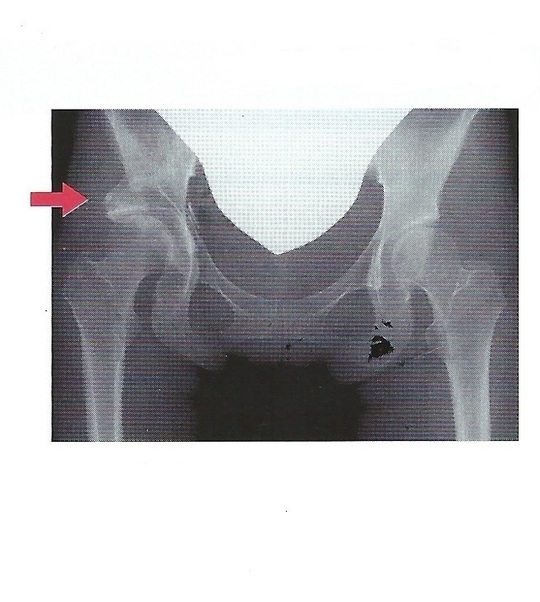

臼蓋形成不全

骨のう胞

【診断】

問診、股関節の誘発痛可動域制限、X線像などで判断します。

正常股関節

臼蓋形成不全症

変形性股関節症